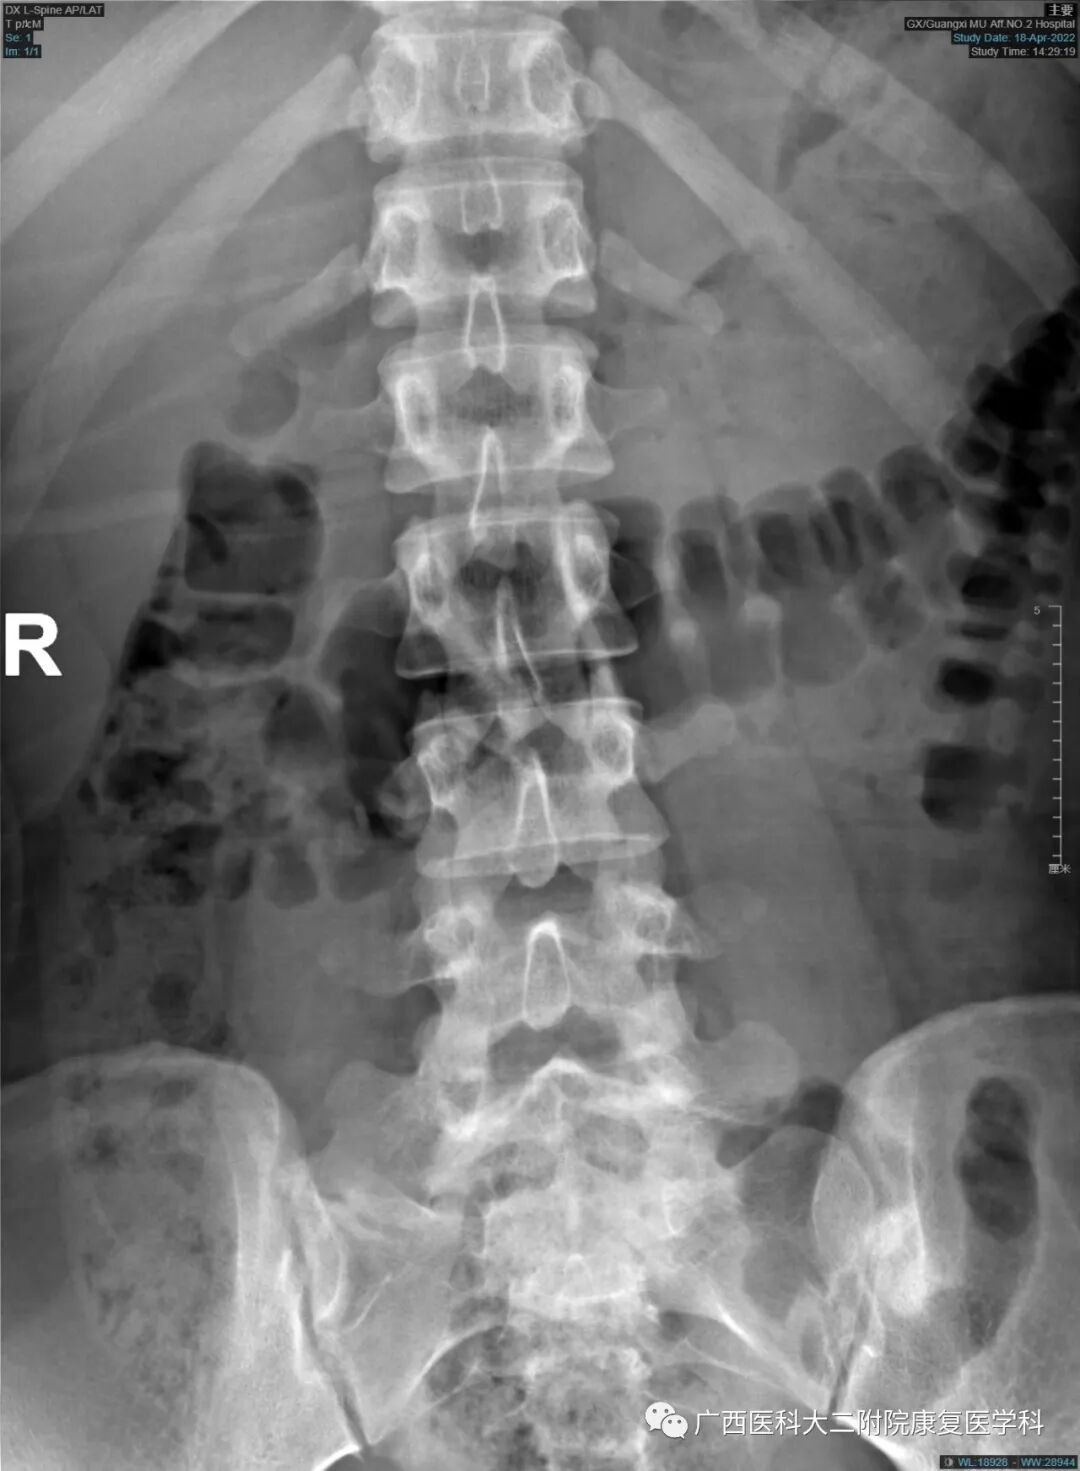

辅助检查:X线片显示L5右侧横突肥大,并假关节形成。

查体:腰椎生理曲度存在,腰肌紧张,L3-L4L4-L5棘上韧带处轻微压痛,无叩击痛,坐位前屈腰骶部有疼痛、躯干旋转有疼痛、屈颈试验(-)直腿抬高试验(-)。

X线